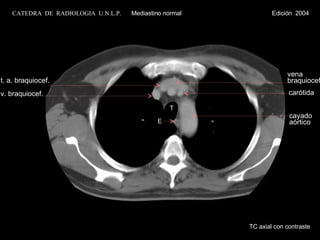

vena braquiocef. T E cayado  aórtico carótida t. a. braquiocef. v. braquiocef. TC axial con contraste CATEDRA  DE  RADIOLOGIA  U.N.L.P.   Mediastino normal  Edición  2004

vena braquiocef. TE cayado aórtico carótida t. a. braquiocef. v. braquiocef. TC axial con contraste CATEDRA DE RADIOLOGIA U.N.L.P. Mediastino normal Edición 2004